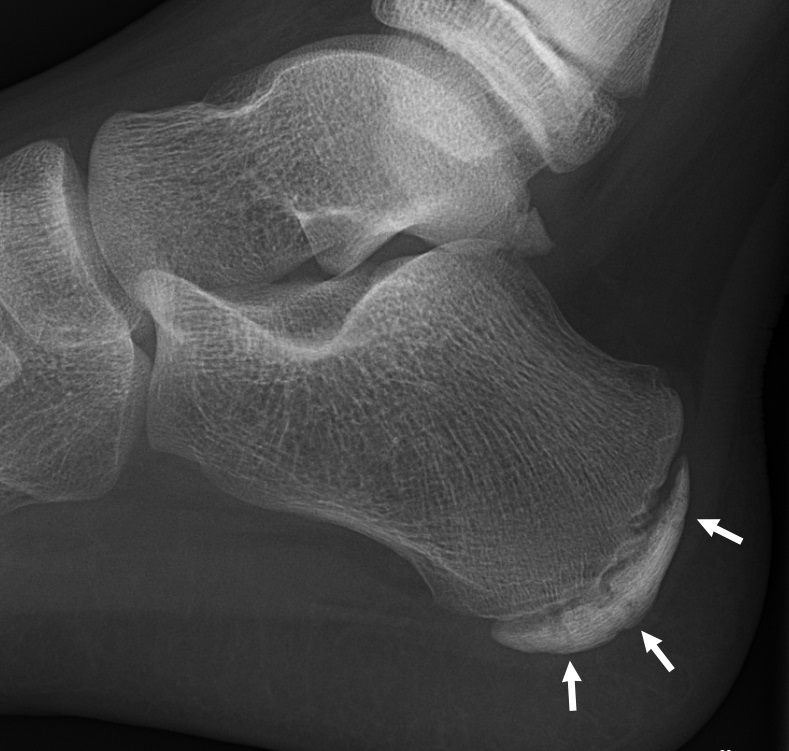

El diagnóstico de la enfermedad de Sever se realiza mediante la exclusión de otras dolencias, lesiones y enfermedades, a través de radiografías y una exploración física de los talones del niño. En algunos casos, pueden ser necesarias pruebas complementarias como ecografías, resonancia magnética, TAC y análisis de sangre.